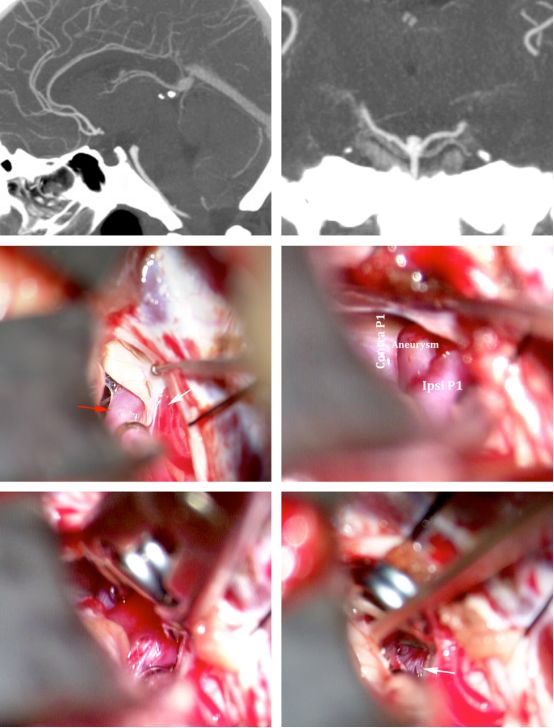

图1:一个低位基底动脉分叉部动脉瘤,瘤颈位于鞍背下方1cm,可经颞下入路显露。

图11:经右侧颞下入路处理一个低位基底动脉分叉部动脉瘤(上排)。动眼神经是该入路的解剖标志;根据动眼神经(手术野中央)来辨认PCA(红色箭号)与SCA(白色箭号)(中排)。两根缝线牵拉天幕,在缝线间小范围切开天幕,有助于近端控制基底动脉主干。用一个直形开窗夹避免损伤同侧P1段及其穿支(下排-白色箭号)。

注:Contra P1:对侧大脑后动脉P1段。Aneurysm:动脉瘤。Ipsi P1:同侧大脑后动脉P1段。